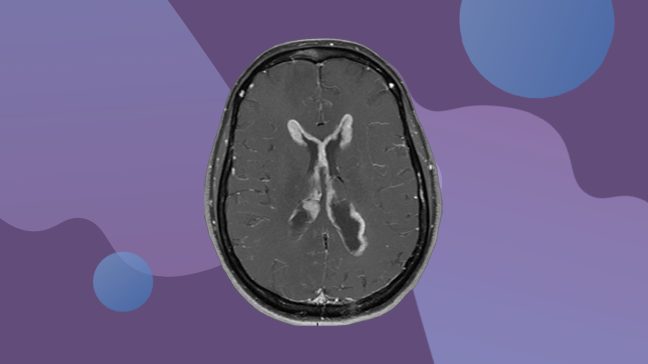

Why my wife had an awake craniotomy to treat glioblastoma

By the time my wife, Priscilla, was diagnosed with an aggressive brain tumor called glioblastoma, her condition was so serious that she needed...

Glioma vs. glioblastoma: What’s the difference?

Glioma and glioblastoma might sound similar, but there are differences between these two types of brain tumor diagnoses.

Here, neuro-oncologist...